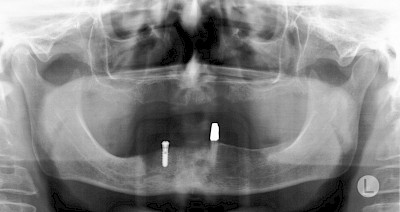

In diesen Fällen kann die Planung mittels verschieden aufwendiger Röntgen-Techniken (Übersichtsaufnahme, DVT) ggf. unter Zuhilfenahme speziell angefertigter Planungsschablonen sinnvoll sein.

Ist nicht genügend Knochen zur Verankerung eines Implantates vorhanden, kann über einen sogenannten Knochenaufbau die Möglichkeit für das Einbringen eines Implantates geschaffen werden. Dazu kann z.B. Knochen aus der Kieferwinkelregion oder auch aus der Kinnregion entnommen und im Bereich der Fehlstellen aufgetragen werden. Auch künstliches Knochenmaterial kann dabei zum Einsatz kommen.

Im Oberkiefer wird – wenn ein Knochenaufbau notwendig ist – der Knochen in der Regel nicht außen "aufgelegt", sondern es wird der Boden der Kieferhöhle entweder über den Implantat-Bohrkanal durch Verdichtung nach oben gedrückt (interner Sinuslift) oder über eine Fensterung der vorderen knöchernen Kieferhöhlenwand kann Knochen im Bereich des Kieferhöhlenbodens eingebracht (externer Sinuslift).